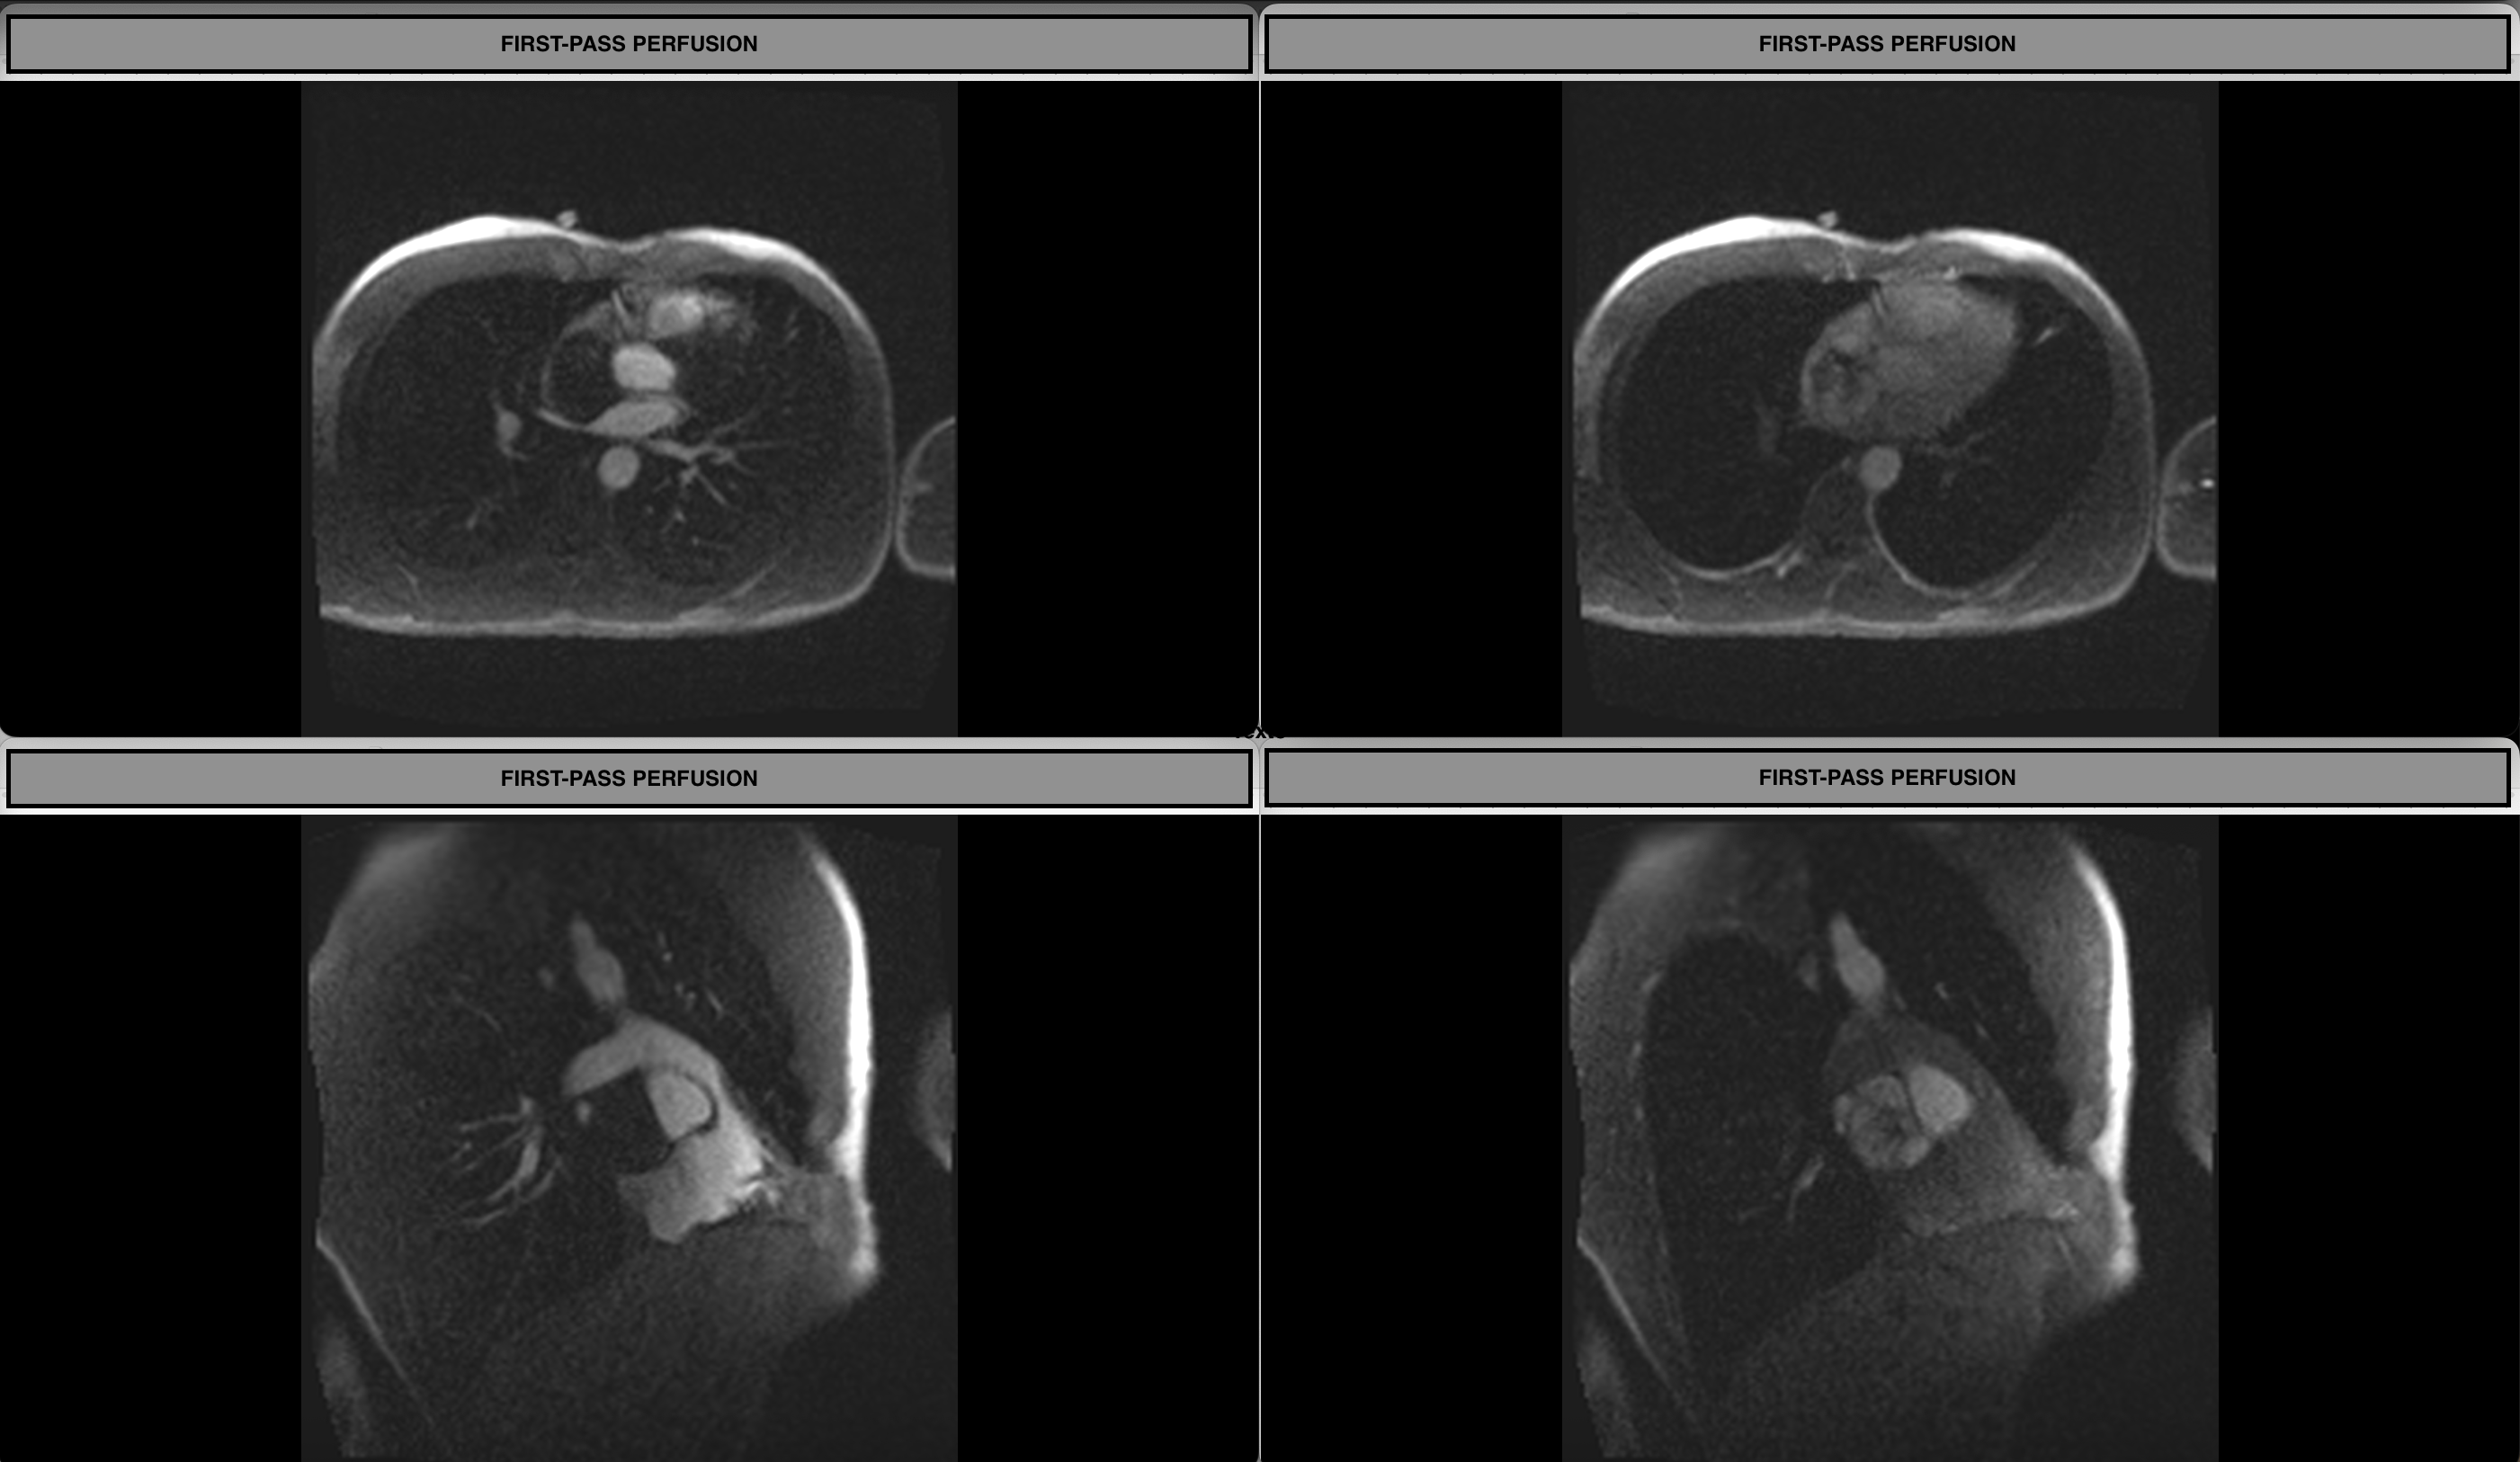

First-pass Perfusion